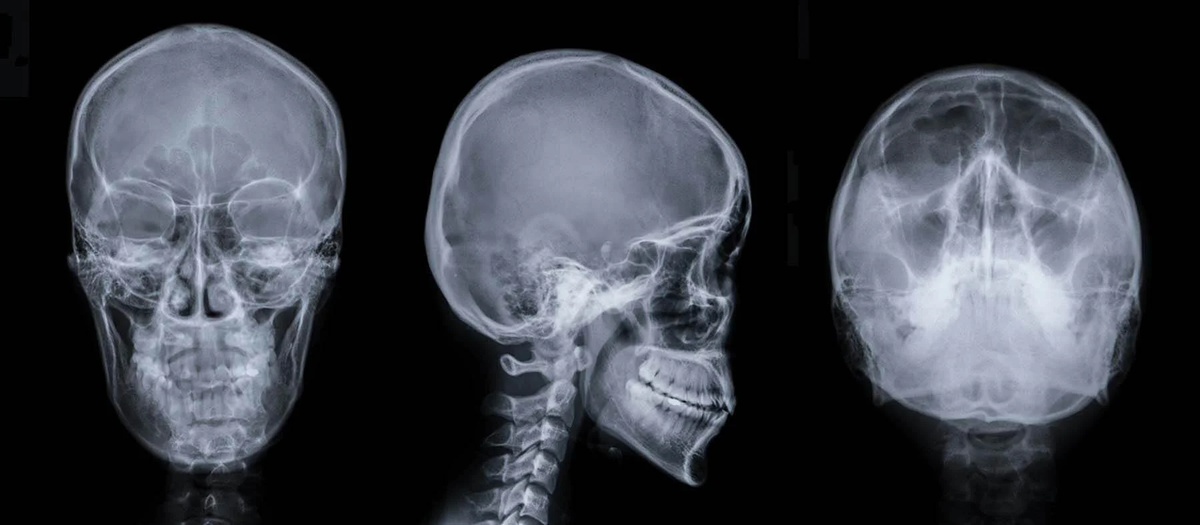

Когда 44-летний француз пришел к врачу, жалуясь на слабость в левой ноге, ему прописали сделать КТ-сканирование, как обычно. Но на снимке было нечто удивительное. В детстве ему поставили диагноз накопления жидкости в головном мозге, и до 14 лет француз ходил с шунтом, после чего его удалили. По-видимому, жидкость продолжала заполнять полость черепа человека в течение следующих 30 лет, медленно разрушая его мозг. Несмотря на то, что мужчина был вполне здоровым и функциональным взрослым человеком, у него осталось только десять процентов мозга. Ученые не могу объяснить, как человек, потерявший большинство областей мозга, вообще может функционировать, не говоря уж о нормальной жизни. Предполагается, что мозг человека находится в постоянном состоянии «переучивания» и что некоторые области мозга, отвечающие за определенные функции, могут быть гораздо более гибкими, чем считалось ранее.